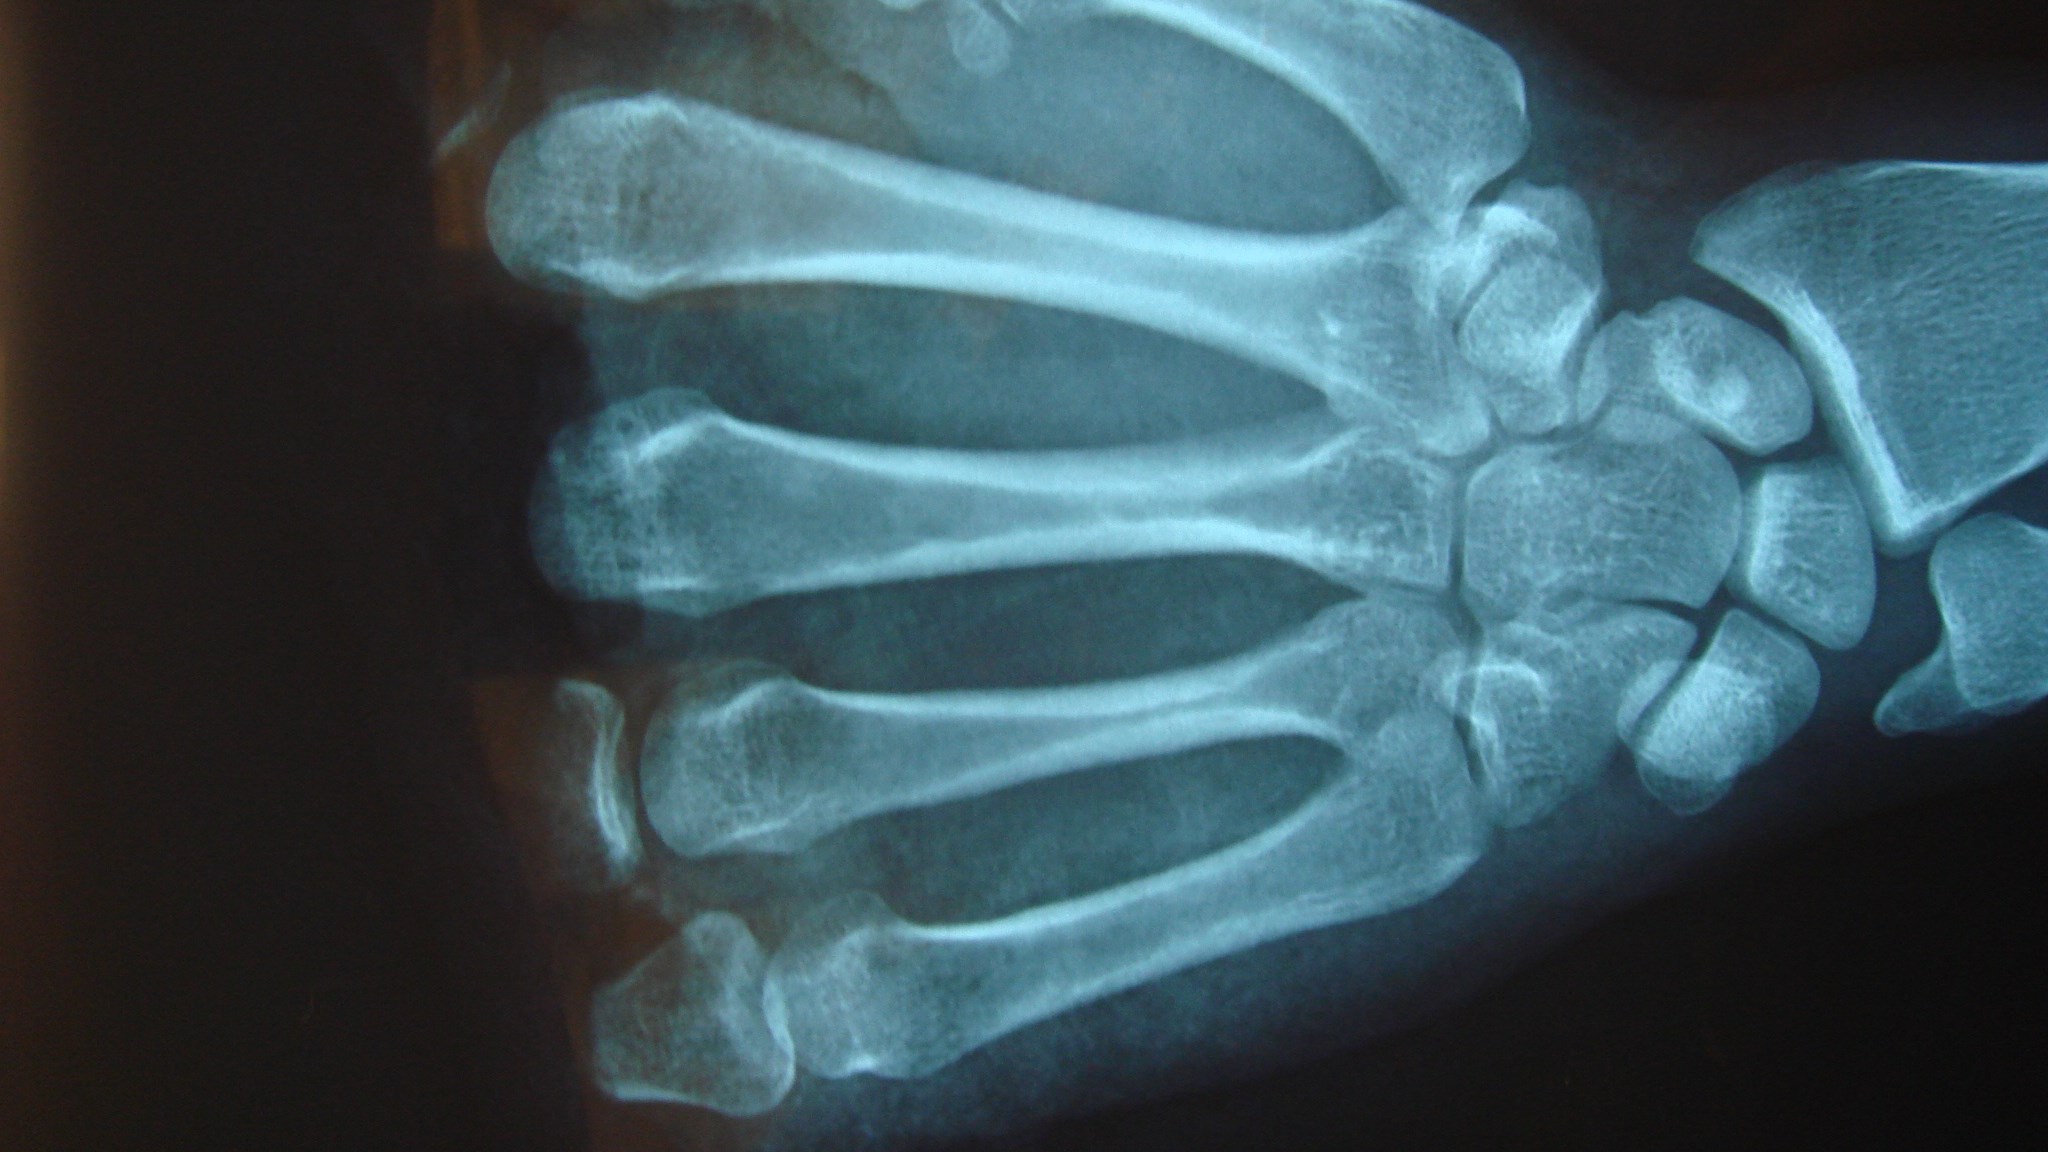

Kompartmentsyndrom

Allmänt

Kompartment syndrom är ett tillstånd där trycket inom ett avgränsat rum överstiger det kapillära perfusionstrycket. Genomblödning av muskler och andra vävnader inom detta kompartment upphör då vilket leder till vävnadsnekros. Observera att det är perfusionstrycket på kapillärnivå som är avgörande. Därför är palpabla pulsar ingen garanti för att det inte föreligger kompartmentsyndrom.

Kompartmentsyndrom är ett urakut tillstånd eftersom det kan räcka med några timmars nedsatt cirkulation för att irreversibla skador skall uppkomma. Det är i första hand muskulaturen som tar skada. Sådana skador medför i ett längre perspektiv till fibros och kontraktur vilket leder till svårbehandlad felställning och stelhet.

Den primära orsaken är ofta en klämskada, ett slag eller ett yttre tryck. En inte ovanlig orsak är att en medvetslös eller kraftigt berusad person har legat och tryckt med huvudet mot underarmen. Det kan också vara en fraktur eller inre blödning som är orsaken till att trycket ökar. När trycket ökar kan skada uppstå som i sin tur ger ökad cellpermeabilitet vilket leder till ödem som i sin tur ökar trycket och en självgenererande ond cirkel uppkommer.

Behandling

Behandlingen är att det avgränsade rummets väggar, dvs. att fascior öppnas kirurgiskt. Många gånger sväller då musklerna fram och huden kan inte slutas. Man får då dra ihop såret så gått det går utan för mycket spänning för att sedan sluta såret när musklerna svällt av. Det finns även teknik för att hålla ihop och successivt sluta sårkanterna mha av ståltråd eller elastiska band.

Hudtransplantat kan senare behövas. När det gäller underarmen finns tre kompartment och både extensor och flexormuskulatur kan drabbas. I handen finns ett tiotal slutna kompartment som alla måste öppnas kirurgiskt om kompartment syndrom misstänks i denna region.

Svårigheterna med kompartment syndrom ligger i diagnostiken. Smärtor efter trauma kan vara svårtolkade. Oproportionerligt svåra smärtor som svarar sämre än förväntat på opioider eller annan stark analgetika är det viktigaste tecknet.

Kan misstanken om kompartmentsyndrom inte motbevisas är behandlingen definitionsmässigt kirurgisk. Fynd som stärker misstanken är ökande smärtor vid högläge. Om smärtorna främst beror på ödem och svullnad minskar de när extremiteten höjs om det däremot föreligger kompartmentsyndrom ökar smärtorna till följd av att perfusionstrycket minskar vid elevation.

Muskulaturen i området är hård och spänd, detta ger också semiflekterade fingrar där man får en uttalad smärtreaktion när man passivt försöker sträcka dem. Parestesier eller känselnedsättning av nerver som passerar genom aktuellt kompartment kan förekomma men det är ett sent och osäkert tecken liksom färgförändringar av huden. Inget avseende skall fästas vid artärpulsationer.

Det finns mätutrustning för att kontrollera vävnadstrycket som med hjälp av nål som sticks ned i aktuellt kompartment. Det kan vara svårt att veta om nålens placering ligger rätt placerad och även andra tekniska svårigheter kan föreligga som gör mätvärdena osäkra. Därför bör mätning främst utföras för att stärka misstanken såvida de inte är helt tydliga.

Mätning är framförallt av värde på patienter som inte kan medverka vid undersökningen exempelvis pga. medvetslöshet. Ett tryck på över 30-40 mm Hg talar för kompartmentsyndrom och det gör även ett tryck inom 30 mmHg av diastoliskt tryck. Det senare är framförallt av värde i sövda patienter på IVA med låga blodtryck.